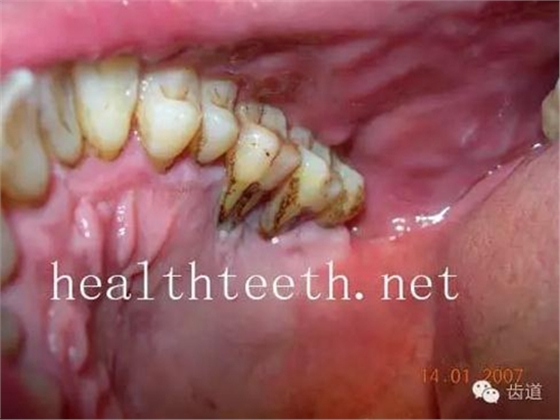

大塊牙石